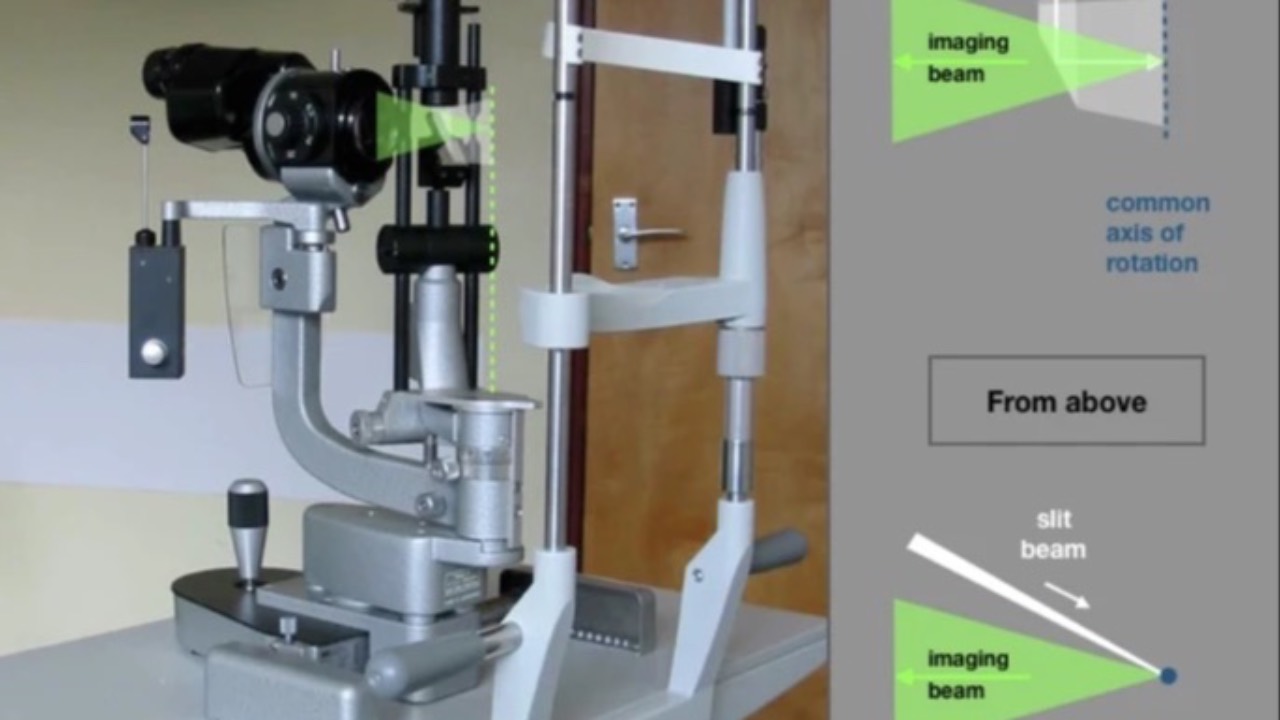

The Slit Lamp is Living Histopathology

A wonderful review...even if you're not a student!

Written by Paul A. R. Meyer, a very impressive review of the slit-lamp was recently published in Nature: Eye. Whether your a seasoned clinician or not, this is a fantastic article celebrating the instrument we use everyday.

The slit-lamp biomicr...